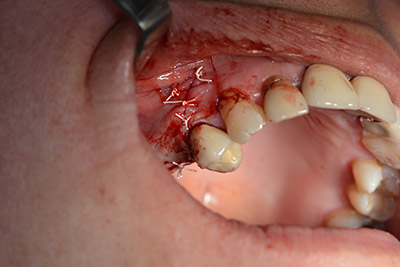

The 59-year-old patient presented with an advanced case of periodontitis, describing an unpleasant feeling and poor taste from the first quadrant in a distal direction. The clinical examination revealed generally enlarged periodontal pockets and very advanced bone atrophy in regions 16 and 14. The radiology confirmed the findings (Fig. 1). Teeth 16 and 14 could not be retained.

Image 1: Orthopantomogram with bone atrophy in region 16–14. *